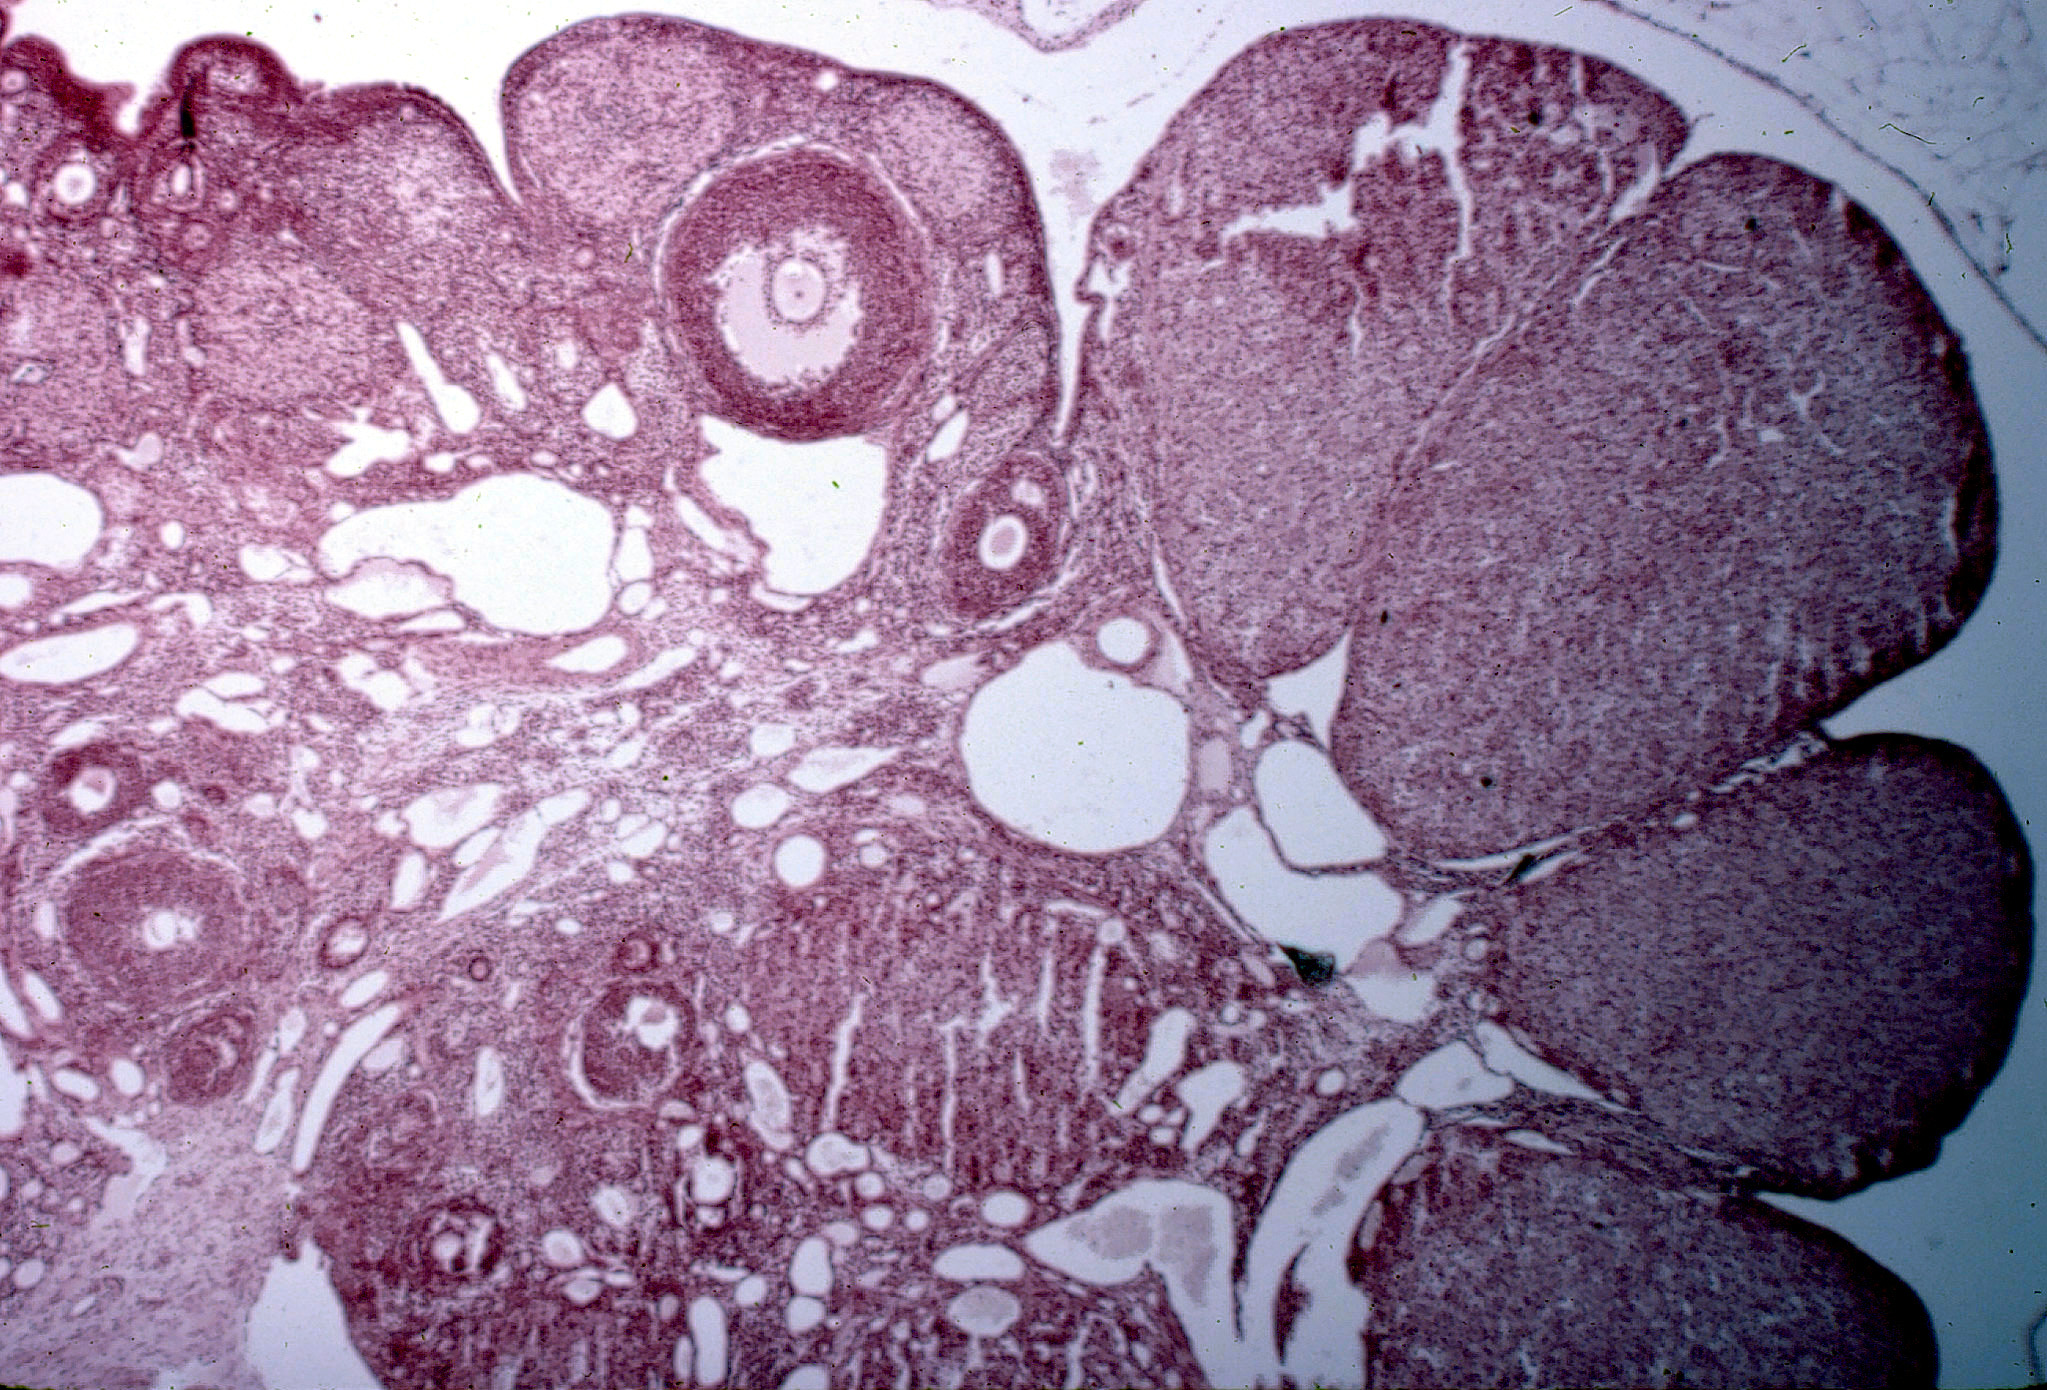

Ovario de rata